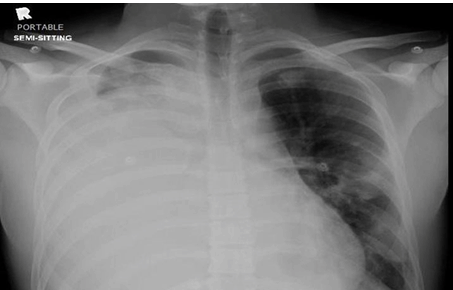

The patient was staying at home suitable for about 1 week, after that he came to the emergency room with chest pain, his ECG showed a picture of pericarditis and by echocardiogram, there was a compression of mediastinal mass compression the right atrium, so he was admitted to the CCU for 48 hours, started on colchicine and symptomatic treatment with clinical improvement and CT chest with contrast was done at that time and showed some improvement (Figure 3), so he discharged stable.

Figure 3: Computed tomography scan of chest with contrast 1 week after 1st cycle of chemotherapy.